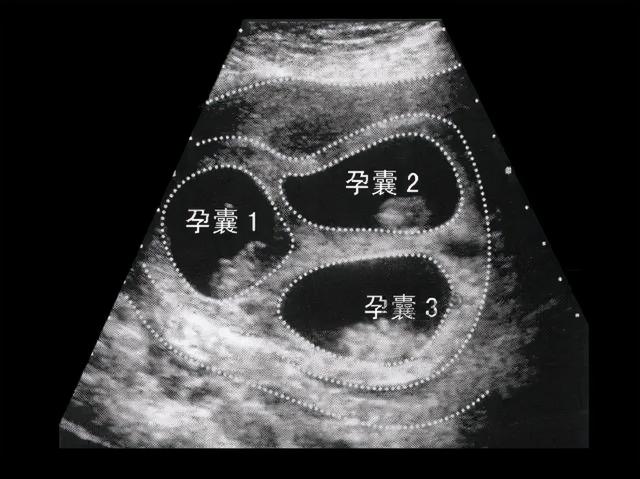

当事人白女士在平台上曝光了一篇《生殖医学科超声检查报告》。报告显示,她的年龄为18岁,8个孕囊清晰可见,但其中只有4个孕囊能看到胚胎和原始心脏搏动,其余4个孕囊看不到原始心脏搏动。